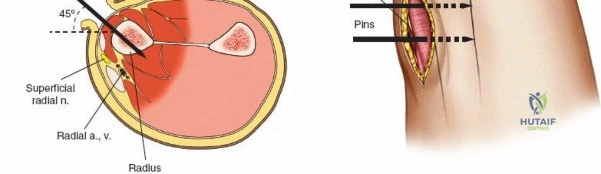

Radius Safe Zones

* Proximal Third: The posterior interosseous nerve (PIN) courses through the supinator muscle. Pin placement in the proximal radius is highly hazardous and generally avoided unless absolutely necessary. If required, a formal dorsal approach (Thompson) is used to visualize and protect the PIN.

* Middle Third: Pins can be placed dorsolaterally. The superficial radial nerve (SRN) and cephalic vein must be protected.

* Distal Third: The SRN emerges from beneath the brachioradialis approximately 9 cm proximal to the radial styloid. Pins are typically placed at a 45-degree angle between the extensor carpi radialis longus (ECRL) and brachioradialis, or directly laterally. A mini-open approach is critical here.

Radius External Fixation

External fixation of the radial diaphysis requires meticulous attention to the superficial radial nerve and the posterior interosseous nerve.

Mid-to-Proximal Radius Pin Placement

1. Supinate the forearm to move the PIN dorsally and radially.

2. Make an incision over the dorsolateral aspect of the radius.

3. Dissect between the extensor carpi radialis brevis (ECRB) and the extensor digitorum communis (EDC).

4. Use retractors to carefully protect the PIN.

5. Insert the tissue sleeve, pre-drill, and place a 4.0 mm pin bicortically.

Distal Radius Pin Placement

1. Identify the interval between the brachioradialis and the ECRL.

2. Make a 2-3 cm longitudinal incision.

3. Carefully identify and retract the superficial radial nerve branches.

4. Place the drill sleeve directly on the radial styloid or slightly proximal, aiming ulnarward and slightly dorsally.

5. Insert 3.0 mm or 4.0 mm pins.